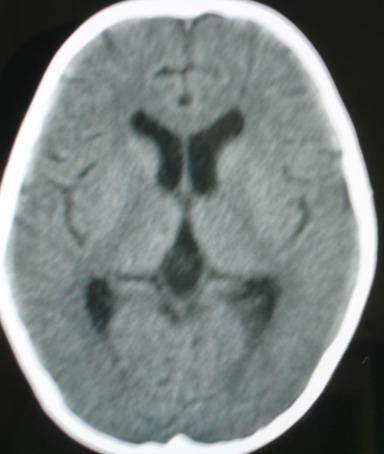

m/8y,右侧眼睑下垂数天,头昏,无呕吐、无外伤史。无搏动性突眼。病人明天来增强。